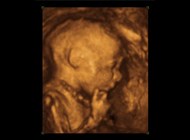

Her kan du læse om dig og din babys udvikling uge for uge. Vi har samlet fakta og sjove ting og krydret det med et lille billede taget her på klinikken i de forskellige uger, så du kan se, hvad der sker inde i livmoderen. Vores graviditetskalender er lavet specielt til dig, som ønsker at vide, hvad du kan forvente uge for uge under din graviditet.

Du kan endnu ikke se babyen på dette billede, men barnet vil denne uge vokse fra 4-9 mm, målt fra hoved mod hale. Målingen af barnet under en ultralydsscanning (kaldes crown-rump-length (CRL)) gør det muligt at bestemme alderen på din graviditet.

Når du kommer til en scanning, kan vi se babyen ved hjælp at hjertet. Det er nemlig muligt nu at se det lille hjerte banke, og at babyen har sat sig rigtigt fast inde i din livmoder. Babyens udvikling kan endnu ikke bestemmes eller ses med det blotte øje med ultralyd, men øjne, næse og mund begynder at træde frem. Arme og ben vil være korte længe endnu, men hænder og fødder begynder at tage form som små luffer.